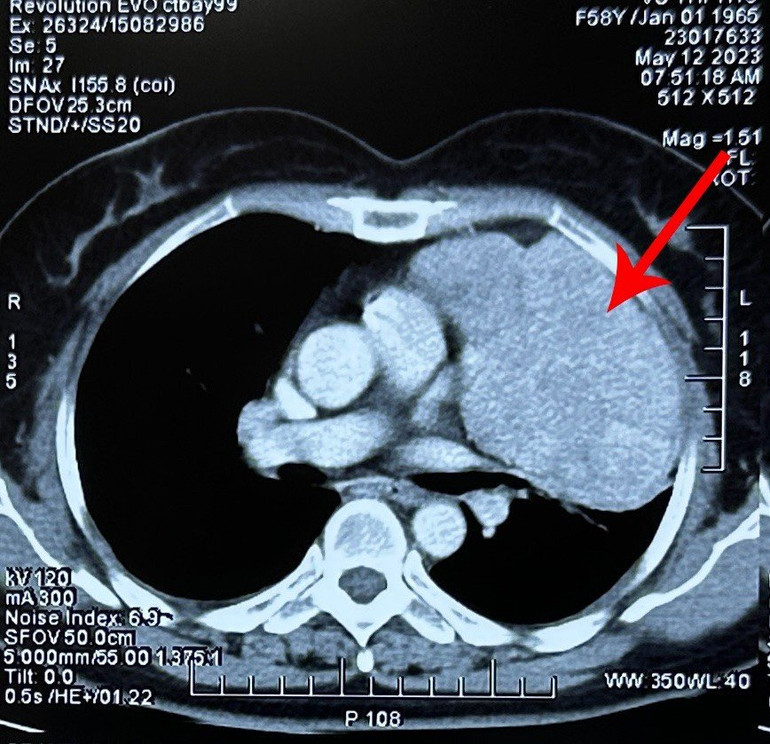

Trước đó, bệnh nhân sức khỏe hoàn toàn bình thường, không có dấu hiệu mệt mỏi, đau đớn hay khó chịu. Khi chuyển đến Bệnh viện Ung Bướu Hà Nội, qua các xét nghiệm chụp chiếu, các bác sĩ xác định khối u kích thước 11x10cm đã chèn ép gây xẹp gần như toàn bộ phổi trái, dính vào màng phổi, màng tim và dịch màng phổi tương đối dày.

| Phim chụp cho thấy khối u chèn ép phổi. |